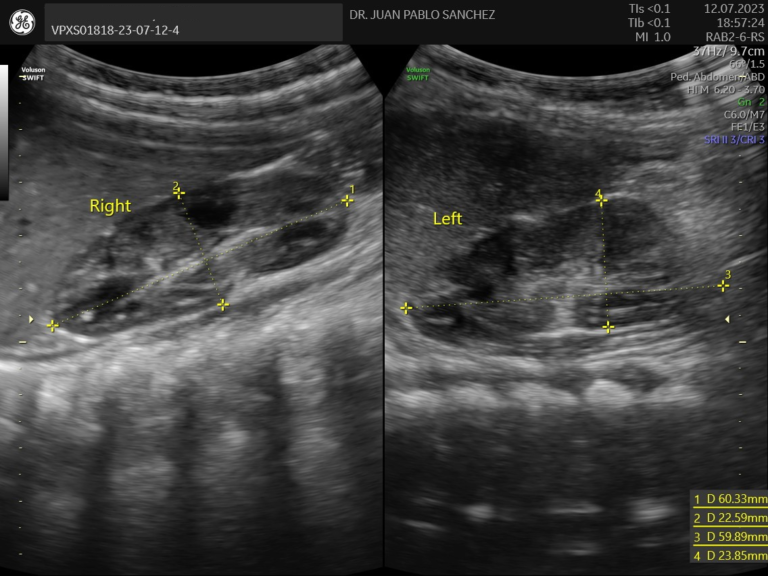

Ecografia Testicular

Estudia los testículos y el escroto en casos de dolor, inflamación o sospecha de torsión testicular o testiculo no descendido. Es rápida y segura, fundamental ante urgencias u otras molestias genitales.